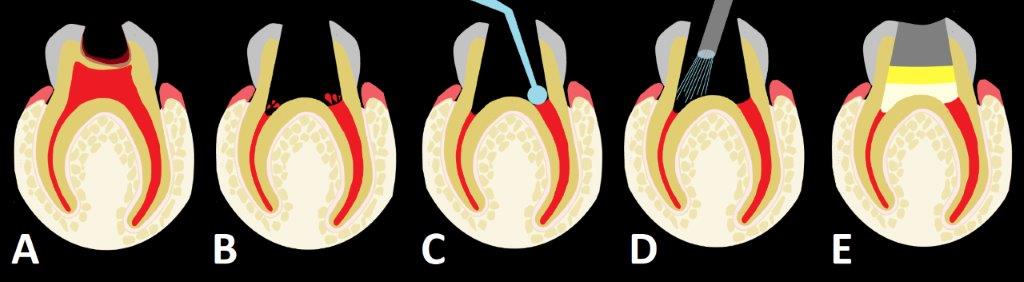

Rycina 1 prezentuje poszczególne etapy amputacji z użyciem siarczanu żelaza, a ryc. 2 to zdjęcia wykonane u 2,5-letniej pacjentki w trakcie zabiegu amputacji miazgi z zastosowaniem preparatu zawierającego w swoim składzie siarczan żelaza (20% siarczan żelaza, Pulpogel, Chema-Elektromet).

Ryc. 2. Zdjęcia wykonane w trakcie zabiegu pulpotomii z zastosowaniem preparatu zawierającego siarczan żelaza u 2,5-letniej pacjentki. Podczas usuwania zębiny próchnicowej w zębie 65 doszło do zranienia miazgi (vulneratio pulpae cariosa). A. Zdjęcie wykonane przed opracowaniem ubytku; B. Zdjęcie wykonane po amputacji miazgi komorowej i uzyskaniu hemostazy w następstwie wtarcia w krwawiącą miazgę korzeniową preparatu zawierającego siarczan żelaza; brunatne skrzepy powstałe w wyniku reakcji żelu z krwią wypłukano sprayem wodno-powietrznym; C. Ząb po założeniu ostatecznego wypełnienia.